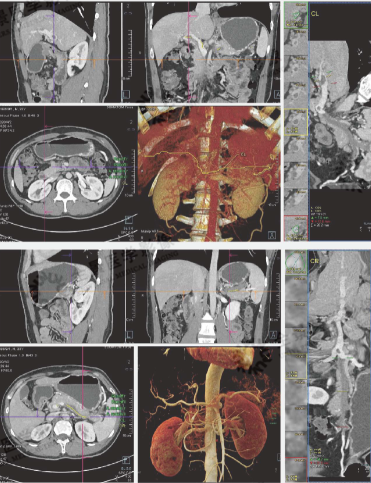

7. 腹部血管成像

影像诊断:门脉主干及左右支起始段多发血栓,大者位于门脉主干及左右支分叉处,伴门脉主干轻度狭窄,门脉右支重度狭窄,分支显示不清;脾静脉及肠系膜上静脉全程、右肾静脉下腔静脉入口段广泛血栓形成。

8. 腹部血管成像

病史:老年男性,右侧小腿疼痛,下肢CTA(VRT)

影像诊断:左下肢肿胀伴皮肤破溃6个月,双下肢CTA显示:两侧骼总动脉、踏内外动脉及双下技广泛动脉粥样硬化伴钙化斑块、软斑形成,以左侧为著,左侧腔后动脉闭塞。

病史:老年男性,右肾占位术前评估,胃动脉CTA(CVRT+MIP)

影像诊断:右肾中部肾癌,肿瘤由右肾动脉供血,主要分支未见明确癌栓征象。